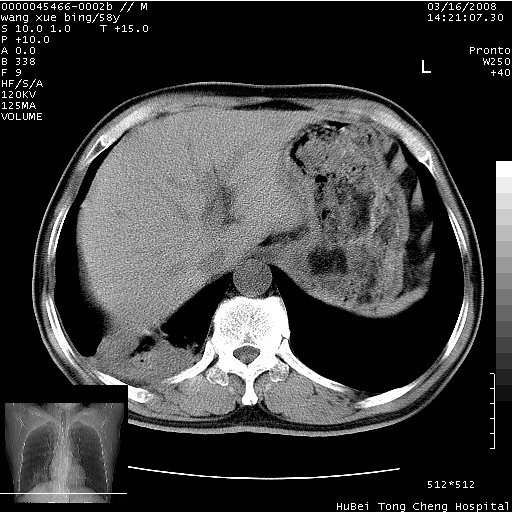

患者 男,58岁。咳嗽、咯血3月余。

胸部cr x线片提示:1)右下肺脓肿。2)右下肺周围型肺癌不排除。建议:行ct扫描检查。

胸部ct轴位平扫(层厚10mm,螺距1.5,重建间隔10mm),图像如下:

右肺下叶团块及不规则空洞,内壁不规则,外缘见粗长毛刺,临近胸膜明显增厚并与病灶关系密切。支持考虑:右肺肺脓肿!建议穿刺病理检查待除外周围型肺癌!

右肺下叶见不规则厚壁空洞,内壁不规则,外缘见粗长毛刺,临近胸膜明显增厚并与病灶关系密切。支持考虑:周围型肺癌!

考虑右下肺中心型肺癌并远端阻塞性炎症及胸膜及纵隔淋巴转移

右肺下叶周围型肺癌伴空洞形成!征象比较明显!分叶、毛刺、胸膜凹陷征、厚壁空洞,壁结节!

影像符合癌性空洞表现,临床如无咳大量浓臭痰史,还是考虑周围型肺癌可能性大。

空洞壁厚,不规则,其内可见壁结节,周围可见毛刺及阻塞性炎变,多考虑癌性病变.

支持癌性空洞并远端阻塞性炎症